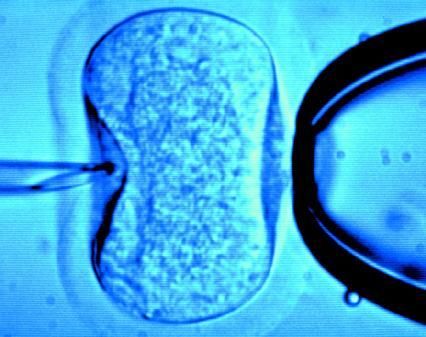

據(jù)英國《每日郵報》1月18日報道,英國一位60歲老婦將成為英國接受試管受精最年長者。這位老婦名叫蘇珊·托勒夫森,是一位退休教師,到今年10月她就滿60歲了。2008年,蘇珊曾去俄羅斯接受試管受精,在英國生下了她的第一個孩子。

倫敦哈利街的私人診所是英國試管嬰兒手術(shù)成功率較高的醫(yī)院之一,醫(yī)生們在上周一同意幫助蘇珊·托勒夫森進行第二次人工受孕。通常情況下,私人診所只在特殊情況下給50歲以上的婦女進行試管受精,例如,患者仍然有月經(jīng)周期。這件事引起了絕經(jīng)后婦女是否有生育權(quán)利的倫理大討論,現(xiàn)在要求提高生育治療年齡上限的呼聲越來越高。

現(xiàn)在,蘇珊·托勒夫森一家人很幸福,丈夫尼克·邁耶是一位公司經(jīng)理,比她小11歲,他們的女兒今年2歲。專家表示,蘇珊很健康,她的女兒如果能有一個兄弟姐妹會更好,于是蘇珊想再次接受試管受精。《星期日郵報》獲悉,倫敦哈利街私人婦女診所的高級工作人員已經(jīng)同意為蘇珊做試管受精,還決定幫助另一位57歲的老婦受孕。(海瀾)